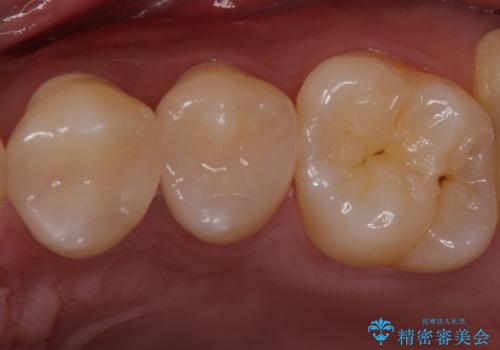

奥歯とはいえ今回のようなケースでは笑った時に銀歯がちらつきます。

白く目立たないセラミックインレーが入ったことで大変喜んでいただけました。